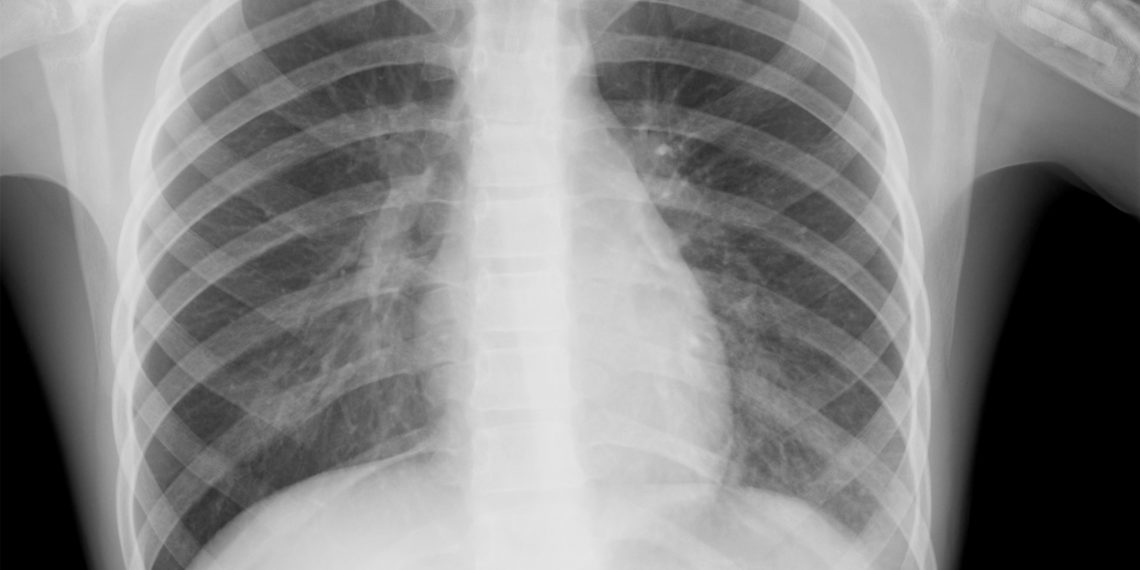

Пневмония — это воспалительное заболевание лёгких. Лёгкие состоят из альвеол — маленьких воздушных камер, которые наполняются воздухом при вдохе и из которых кислород поступает в кровь. Через них же кровь избавляется от углекислого газа. При пневмонии альвеолы заполняются жидкостью или гноем, и больной не может полноценно дышать.